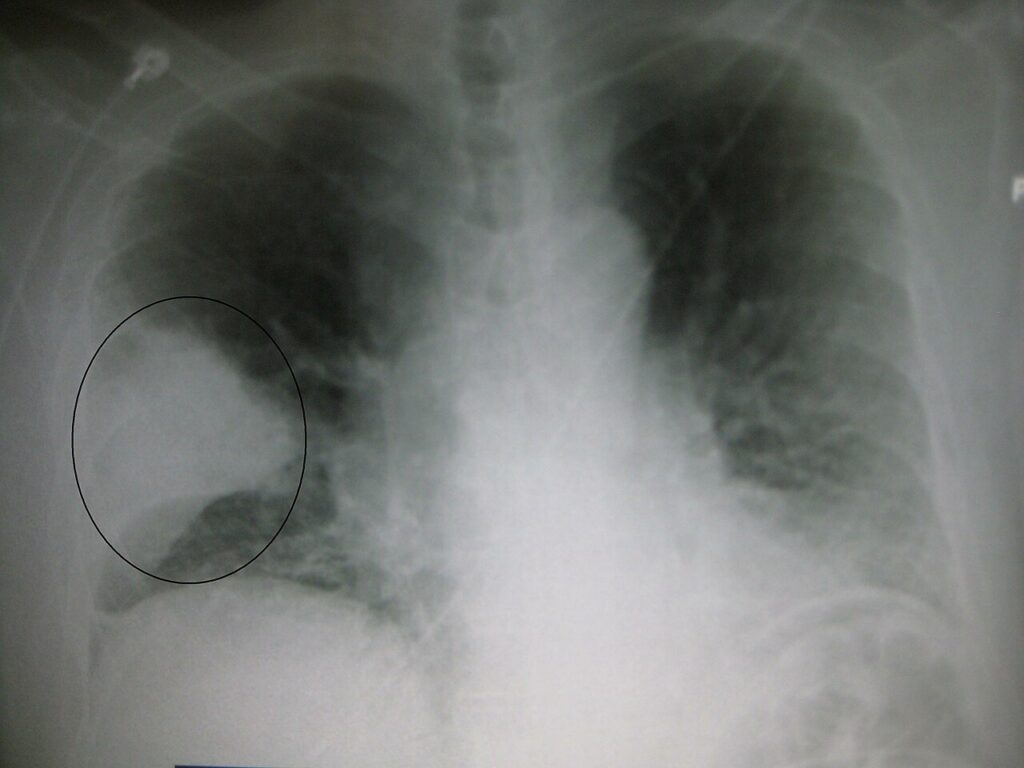

RTG klatki piersiowej

Zdjęcie rentgenowskie klatki piersiowej, radiogram klatki piersiowej – badanie radiologiczne polegające na przepuszczeniu przez klatkę piersiową kontrolowanych dawek promieni rentgenowskich, rzutowanych na prostopadłą płaszczyznę z detektorem tych promieni. >>>

RTG klatki piersiowej to badanie diagnozujące także w innych stanach chorobowych, jak np.: beryloza, niedomykalność zastawki mitralnej, wypadanie płatka zastawki mitralnej, zwężenie zastawki aortalnej, ornitoza, legionelloza, nokardioza, glistnica, bąblowica.